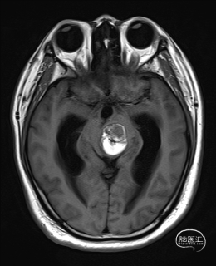

术前MRI检查

术前MRI检查提示左侧丘脑中脑海绵状血管瘤并卒中,梗阻性脑积水;

诊断:1.左侧丘脑中脑海绵状血管瘤并卒中,2.梗阻性脑积水;

根据MRI及DTI显示,只有在丘脑与上丘之间的点(dot)进入病变才可能在切除病变时最大程度保护神经功能,由于上述原因,该“点”在术中显露极其困难,虽有导航指引,电生理监测的条件下,对术者的耐心、技术、经验及体能依然是极大的挑战;

本例患者磁共振检查清晰显示病变位于左侧丘脑中脑区域,且位于丘脑内下方向中脑顶盖延续,病变的上部、前部、外侧部都有重要的神经组织,因此,手术从上方、前方、外侧方向切除病变均难以实施;

从后方有POPPEN入路、Krause入路等,但是因为病变并未充分向松果体区、大脑大静脉后方突出,有大脑大静脉复合体的阻挡,POPPEN入路有较大的难度显露及切除病变,残留的可能性比较大;传统显微镜下进行的幕下小脑上入路在病变的显露及切除上依然有较大的难度。